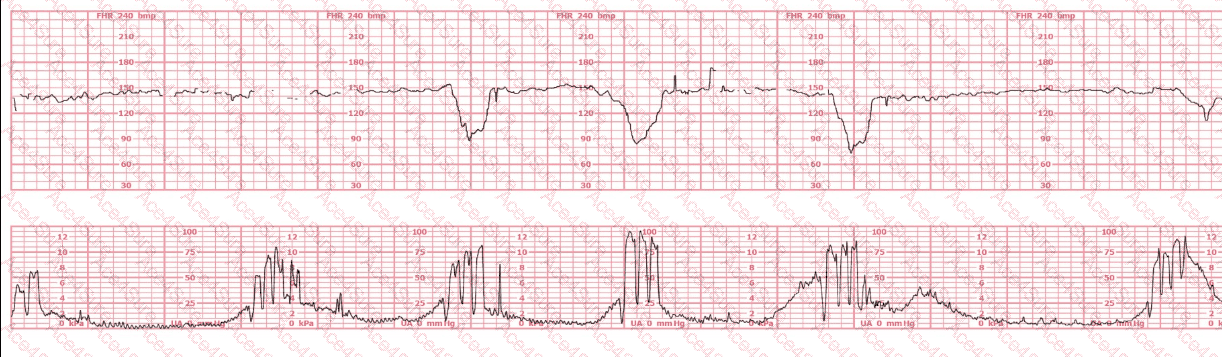

According to the NCC C-EFM Exam Outline and AWHONN Fetal Heart Monitoring (5th & 6th ed.), recurrent variable decelerations with progressive reduction in variability reflect worsening fetal hypoxia, especially when coupled with prolonged second stage and arrest of descent.

“Minimal variability with recurrent decelerations indicates inability of the fetus to maintain adequate oxygenation.”

“Failure of descent in second stage with non-reassuring patterns requires operative delivery.”

Here, the fetus is OP, descent has arrested, and FHR is non-reassuring. This contraindicates vacuum extraction.